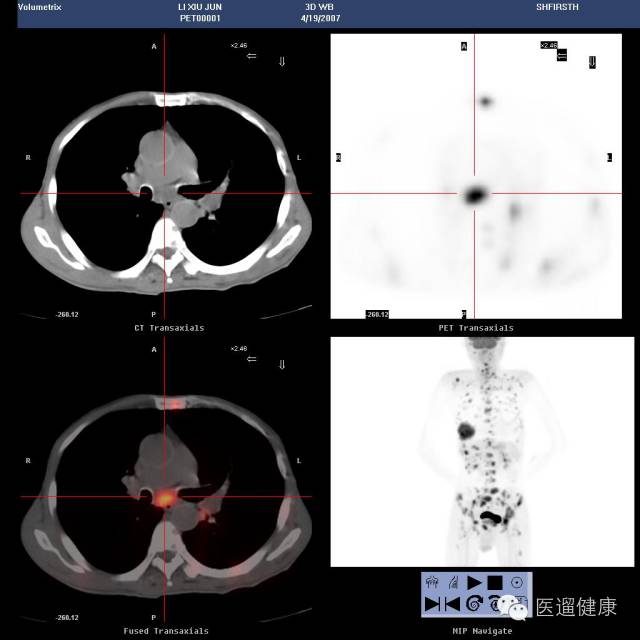

案例三、

PET/CT协助淋巴瘤首次分期病例

病患:女,64岁,左眼疼痛、视力下降一月余。

外院MRI提示左蝶筛窦炎。

左筛窦内窥镜手术,病理:左筛窦NHL(非霍奇金淋巴瘤)(DLBCL)。

入院时初步分期:IA期。

PET/CT显像目的:协助临床准确分期。

分期上调为IIIA期

左海绵窦增宽,左视神经孔受压,前床突骨质硬化并边缘骨质侵蚀,SUV最大值约13.2

该病例通过

PET/CT后分期上调为IIIA期